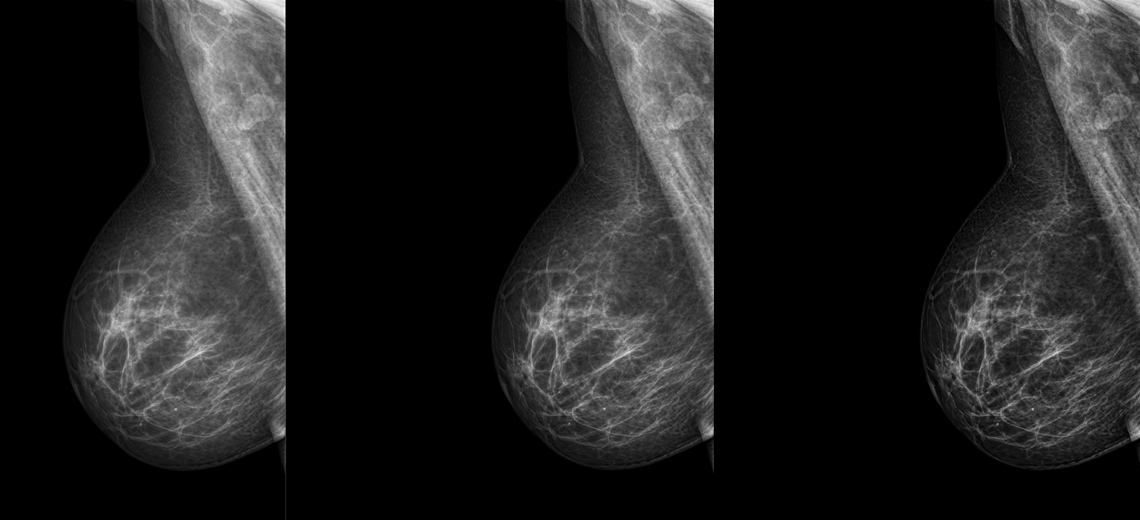

Obrazy Kliniczne Planmed Clarity 3D